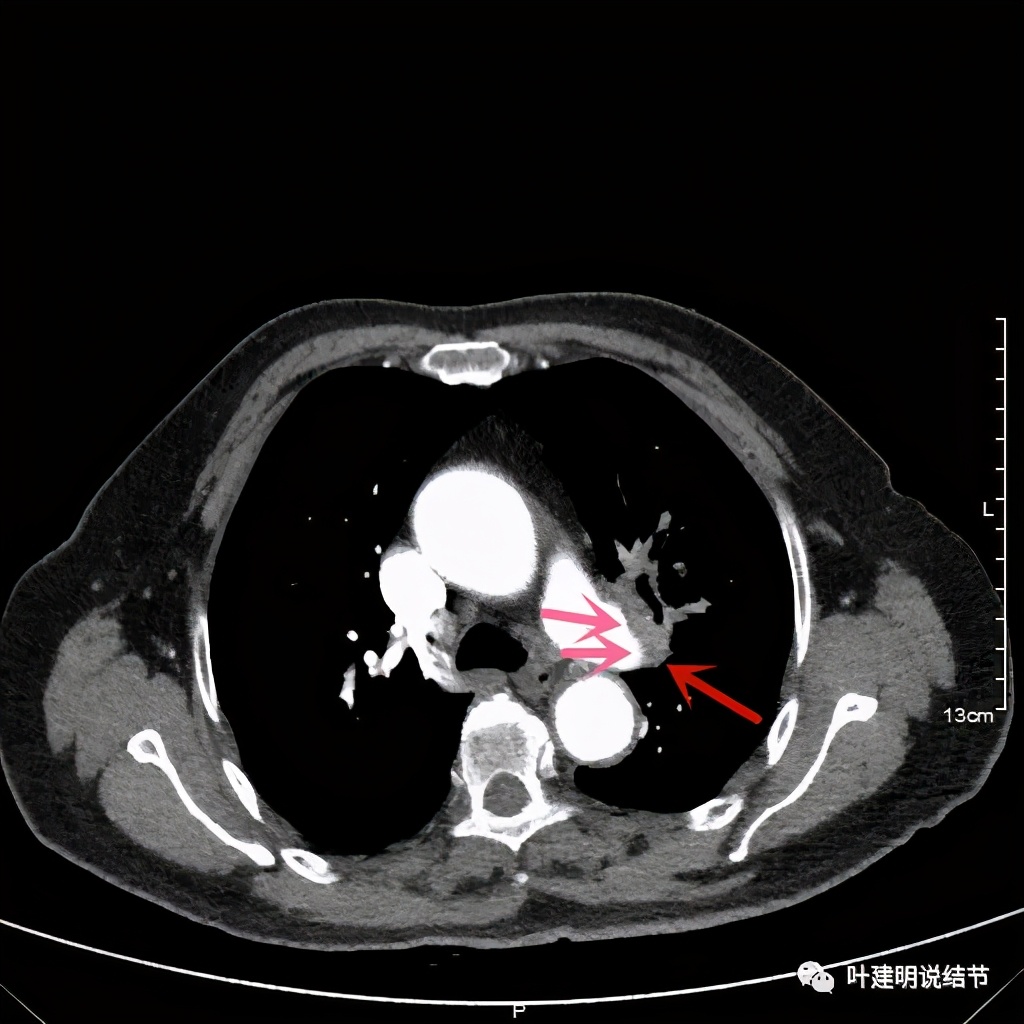

上图示肿瘤部位仍与肺动脉关系密切,似乎未能脱开,红色示肿瘤处

我样的治疗效果,显然超出了我们之前的预期,那么接下来拟选择行手术治疗,初定左上叶袖式肺叶切除加淋巴结清扫,但因为肺门区仍有软组织影,与肺动脉的关系仍密切,肿瘤与肺动脉间能否游离开来还是未知数,但至少得努力争取,鉴于患者年纪虽大,肺功能指标尚可,血气分析也基本正常,所以与患方沟通后确定行手术探查,但也也说明有万一全肺切除的可能(虽然这种可能性较小)。